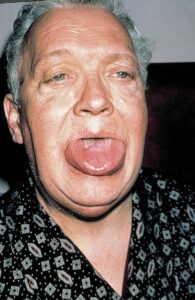

Angioedema is the swelling of deep dermis, subcutaneous or submucosal tissue due to vascular leakage.1 It was first described in 1586.2 Other terms, such as giant urticaria,3 Quincke edema,4 and angioneurotic edema,5 have also been used in the past to describe this condition. Clinically, angioedema is usually nonpitting and nonpruritic. The area of involvement is often skin-colored or slightly erythematous. Depending on the area of swelling, pain can be absent or mild, as in most peripheral or facial swelling, or can be very severe, as in gastrointestinal angioedema. Laryngeal swelling is life-threatening. It should be treated as a medical emergency.

Patients usually describe swelling of the face (eg, eyelids, lips), tongue, hands, and feet. It can be acute or chronic, and each episode of angioedema may last a few hours to a few days. A local burning sensation and pain can be observed without pronounced itchiness or local erythema. Abdominal pain can sometimes be the only presenting symptom of angioedema. Throat tightness, voice changes, and trouble breathing may indicate airway involvement.

Uvula or tongue swelling can be visualized directly (see image below). However, a laryngoscopy is needed to assess laryngeal or vocal cord involvement.